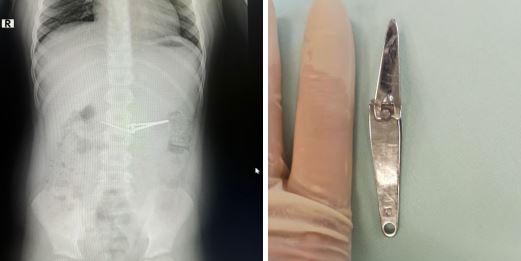

С необычным случаем столкнулись врачи ГКБ № 17 в Уфе. По данным Минздрава Башкирии, врачам пришлось вытаскивать из желудка 6-летнего пациента щипцы для стрижки ногтей.

Мальчику по экстренным показаниям провели фиброгастроскопию под общим обезболиванием с применением специальной эндокорзины. Она позволила врачам безопасно захватить и извлечь щипцы.